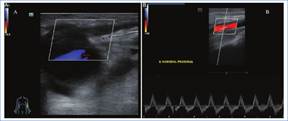

Robo arterial

Se produce por un descenso de la perfusión distal arterial debido a una preferencia de salida del flujo arterial a través de la vena del acceso vascular, de menor resistencia que el lecho arterial distal1. Es más frecuente en fístulas nativas proximales o injertos protésicos, aumentando el riesgo en pacientes ancianos o con múltiple comorbilidad4. En general, el fenómeno de robo es clínicamente silente; los síntomas aparecen cuando claudican los mecanismos compensatorios para mantener la irrigación arterial periférica4.

En el Doppler color se evidencia flujo invertido completo o parcial (solo durante la diástole) en la arteria distal, y mediante la compresión momentánea de la FAV se reestablece el sentido anterógrado normal del flujo (Fig. 4)4,5.